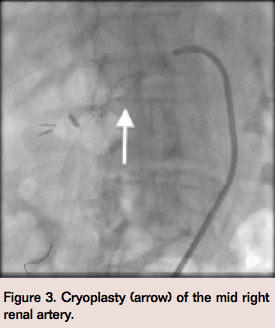

An 8-Fr renal double curved (RDC) guiding catheter (Cordis) was used to selectively engage the right renal artery. Optical coherence tomography (OCT) was performed using a Dragonfly catheter (St. Jude Medical), which confirmed longitudinal intimal irregularities with a reference vessel size of 5.75 mm (Figure 2). A PolarCath 6 x 20 mm balloon (Boston Scientific) was used to perform cryoplasty of the mid-right renal artery (Figure 3).